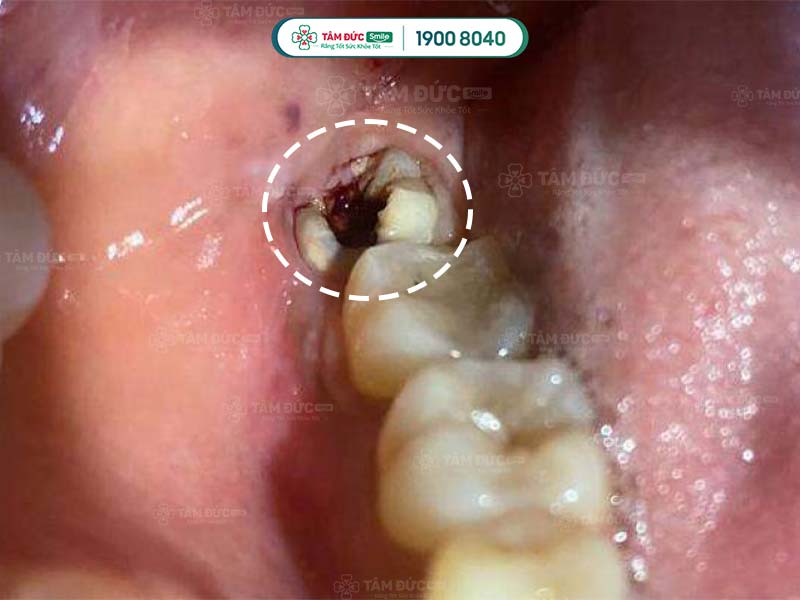

Răng bị sâu gây nhiễm trùng lan đến vòm họng

Khi bị nhiễm trùng huyệt răng, vi khuẩn có thể xâm nhập vào cổ họng theo nhiều con đường khác nhau. Chẳng hạn như:

Nhiễm trùng huyệt răng có thể biểu hiện bằng các triệu chứng như sưng tấy, đau nhức, chảy mủ, có mùi hôi khó chịu,... Nếu trường hợp này không được xử lý kịp thời, vi khuẩn có thể lây lan sang các vùng xung quanh, đặc biệt là vùng cổ họng.